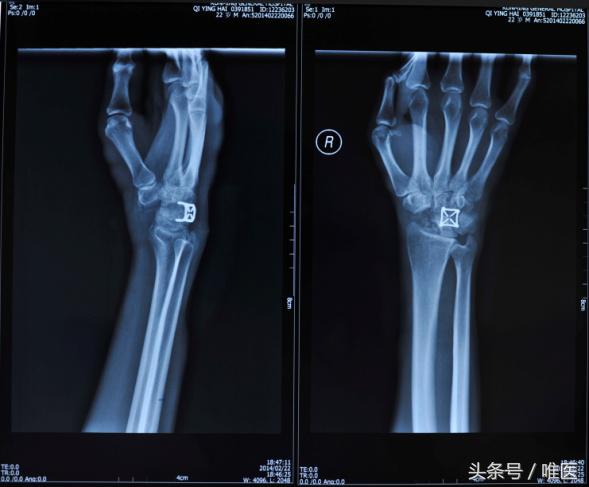

4.记忆合金钉脚固定器+辅助克氏针内固定

国内徐永清教授利用自行研发的镍钛记忆合金钉脚固定器固定腕舟骨骨折,将月骨周围脱位复位后辅助克氏针固定防止再次脱位,徐永清教授介绍对于新鲜的经舟骨月骨周围脱位,往往将脱位复位,并固定舟骨骨折后,大多时候是可以不用加以克氏针固定防止再次脱位的,因为复位固定舟骨后关节不容易再次脱位,必要时可以辅助石膏固定三周即可。治疗陈旧性的经舟骨月骨周围脱位,记忆合金钉脚固定器在处理陈旧的舟骨骨折方面有很好的疗效,因为它的加压作用是值得肯定的,且结合术中植骨,更加减少舟骨骨不连的几率。